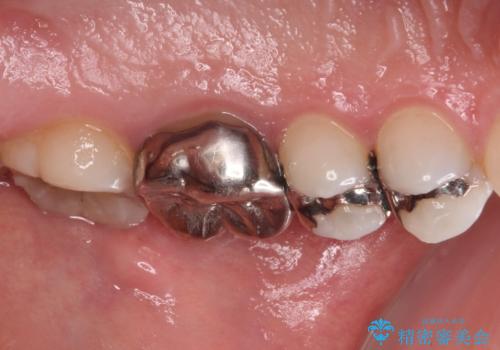

- 奥歯の銀歯が外れたことをきっかけに、全ての銀歯をセラミックに替えたいとのことで来院された患者様です。

第一大臼歯4本と、メタルインレーが装着されている2歯をセラミッククラウンならびにセラミックインレーにて補綴治療・修復治療を行うこととしました。